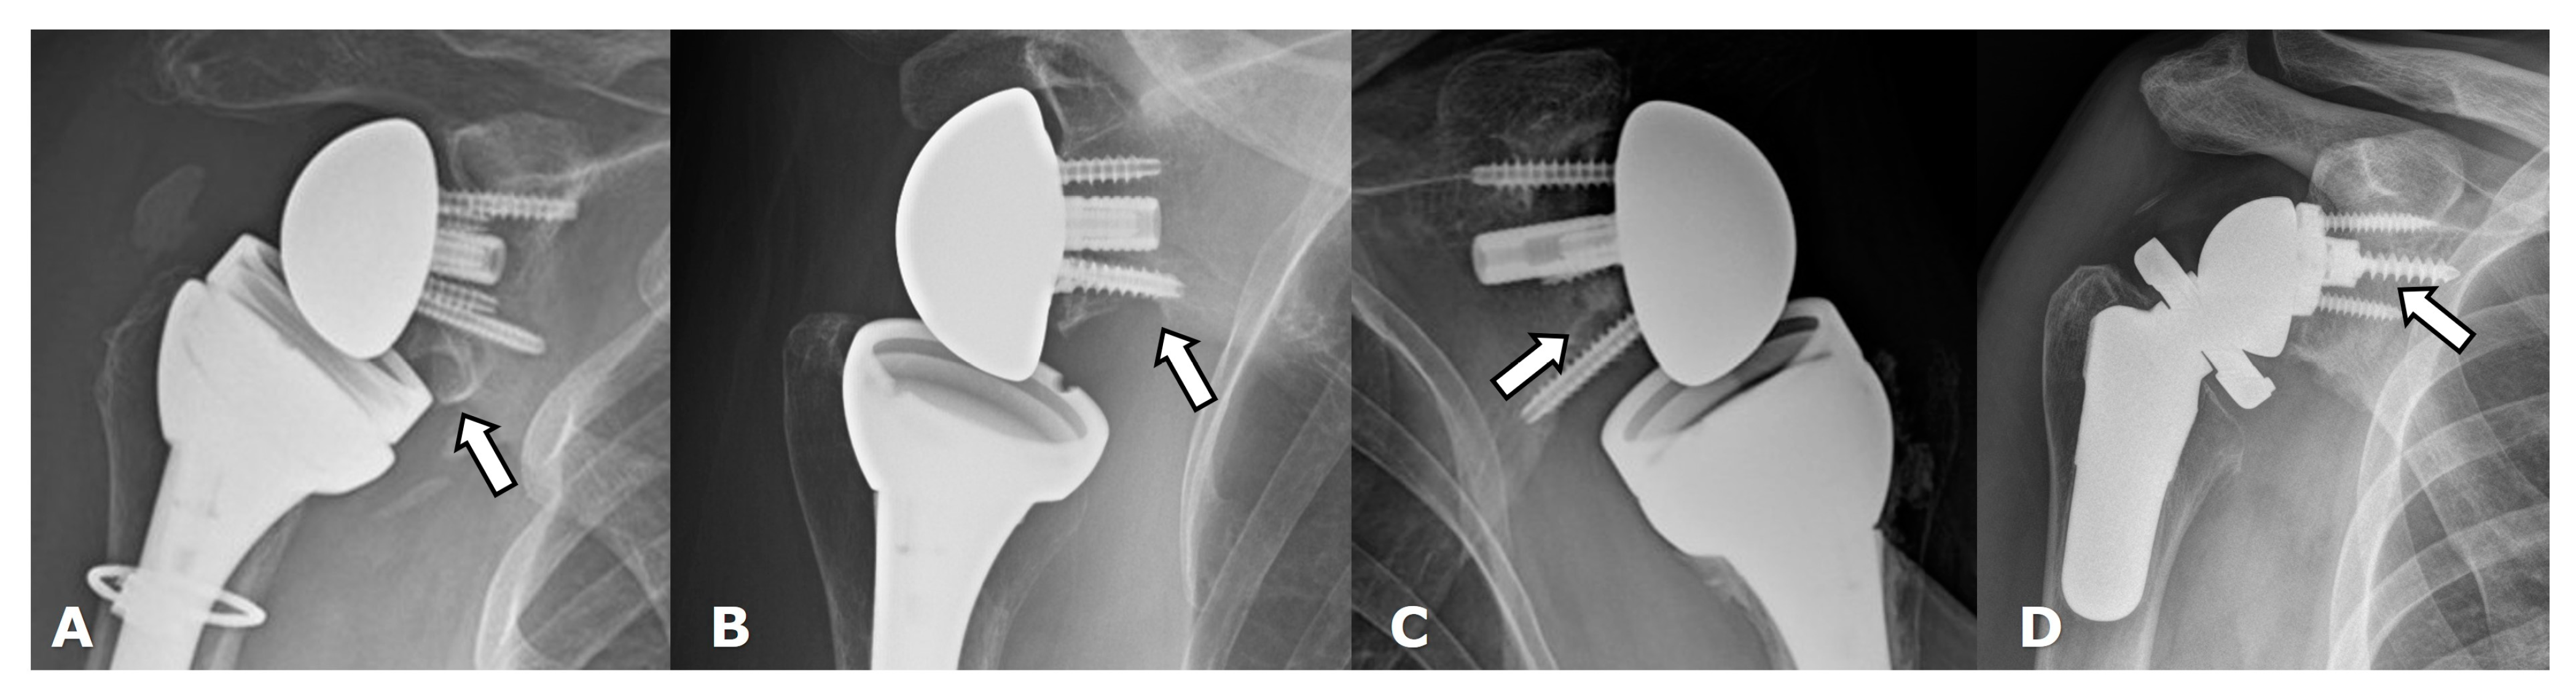

5.2. Reverse Arthroplasty

Reverse Total Shoulder Arthroplasty (RTSA)